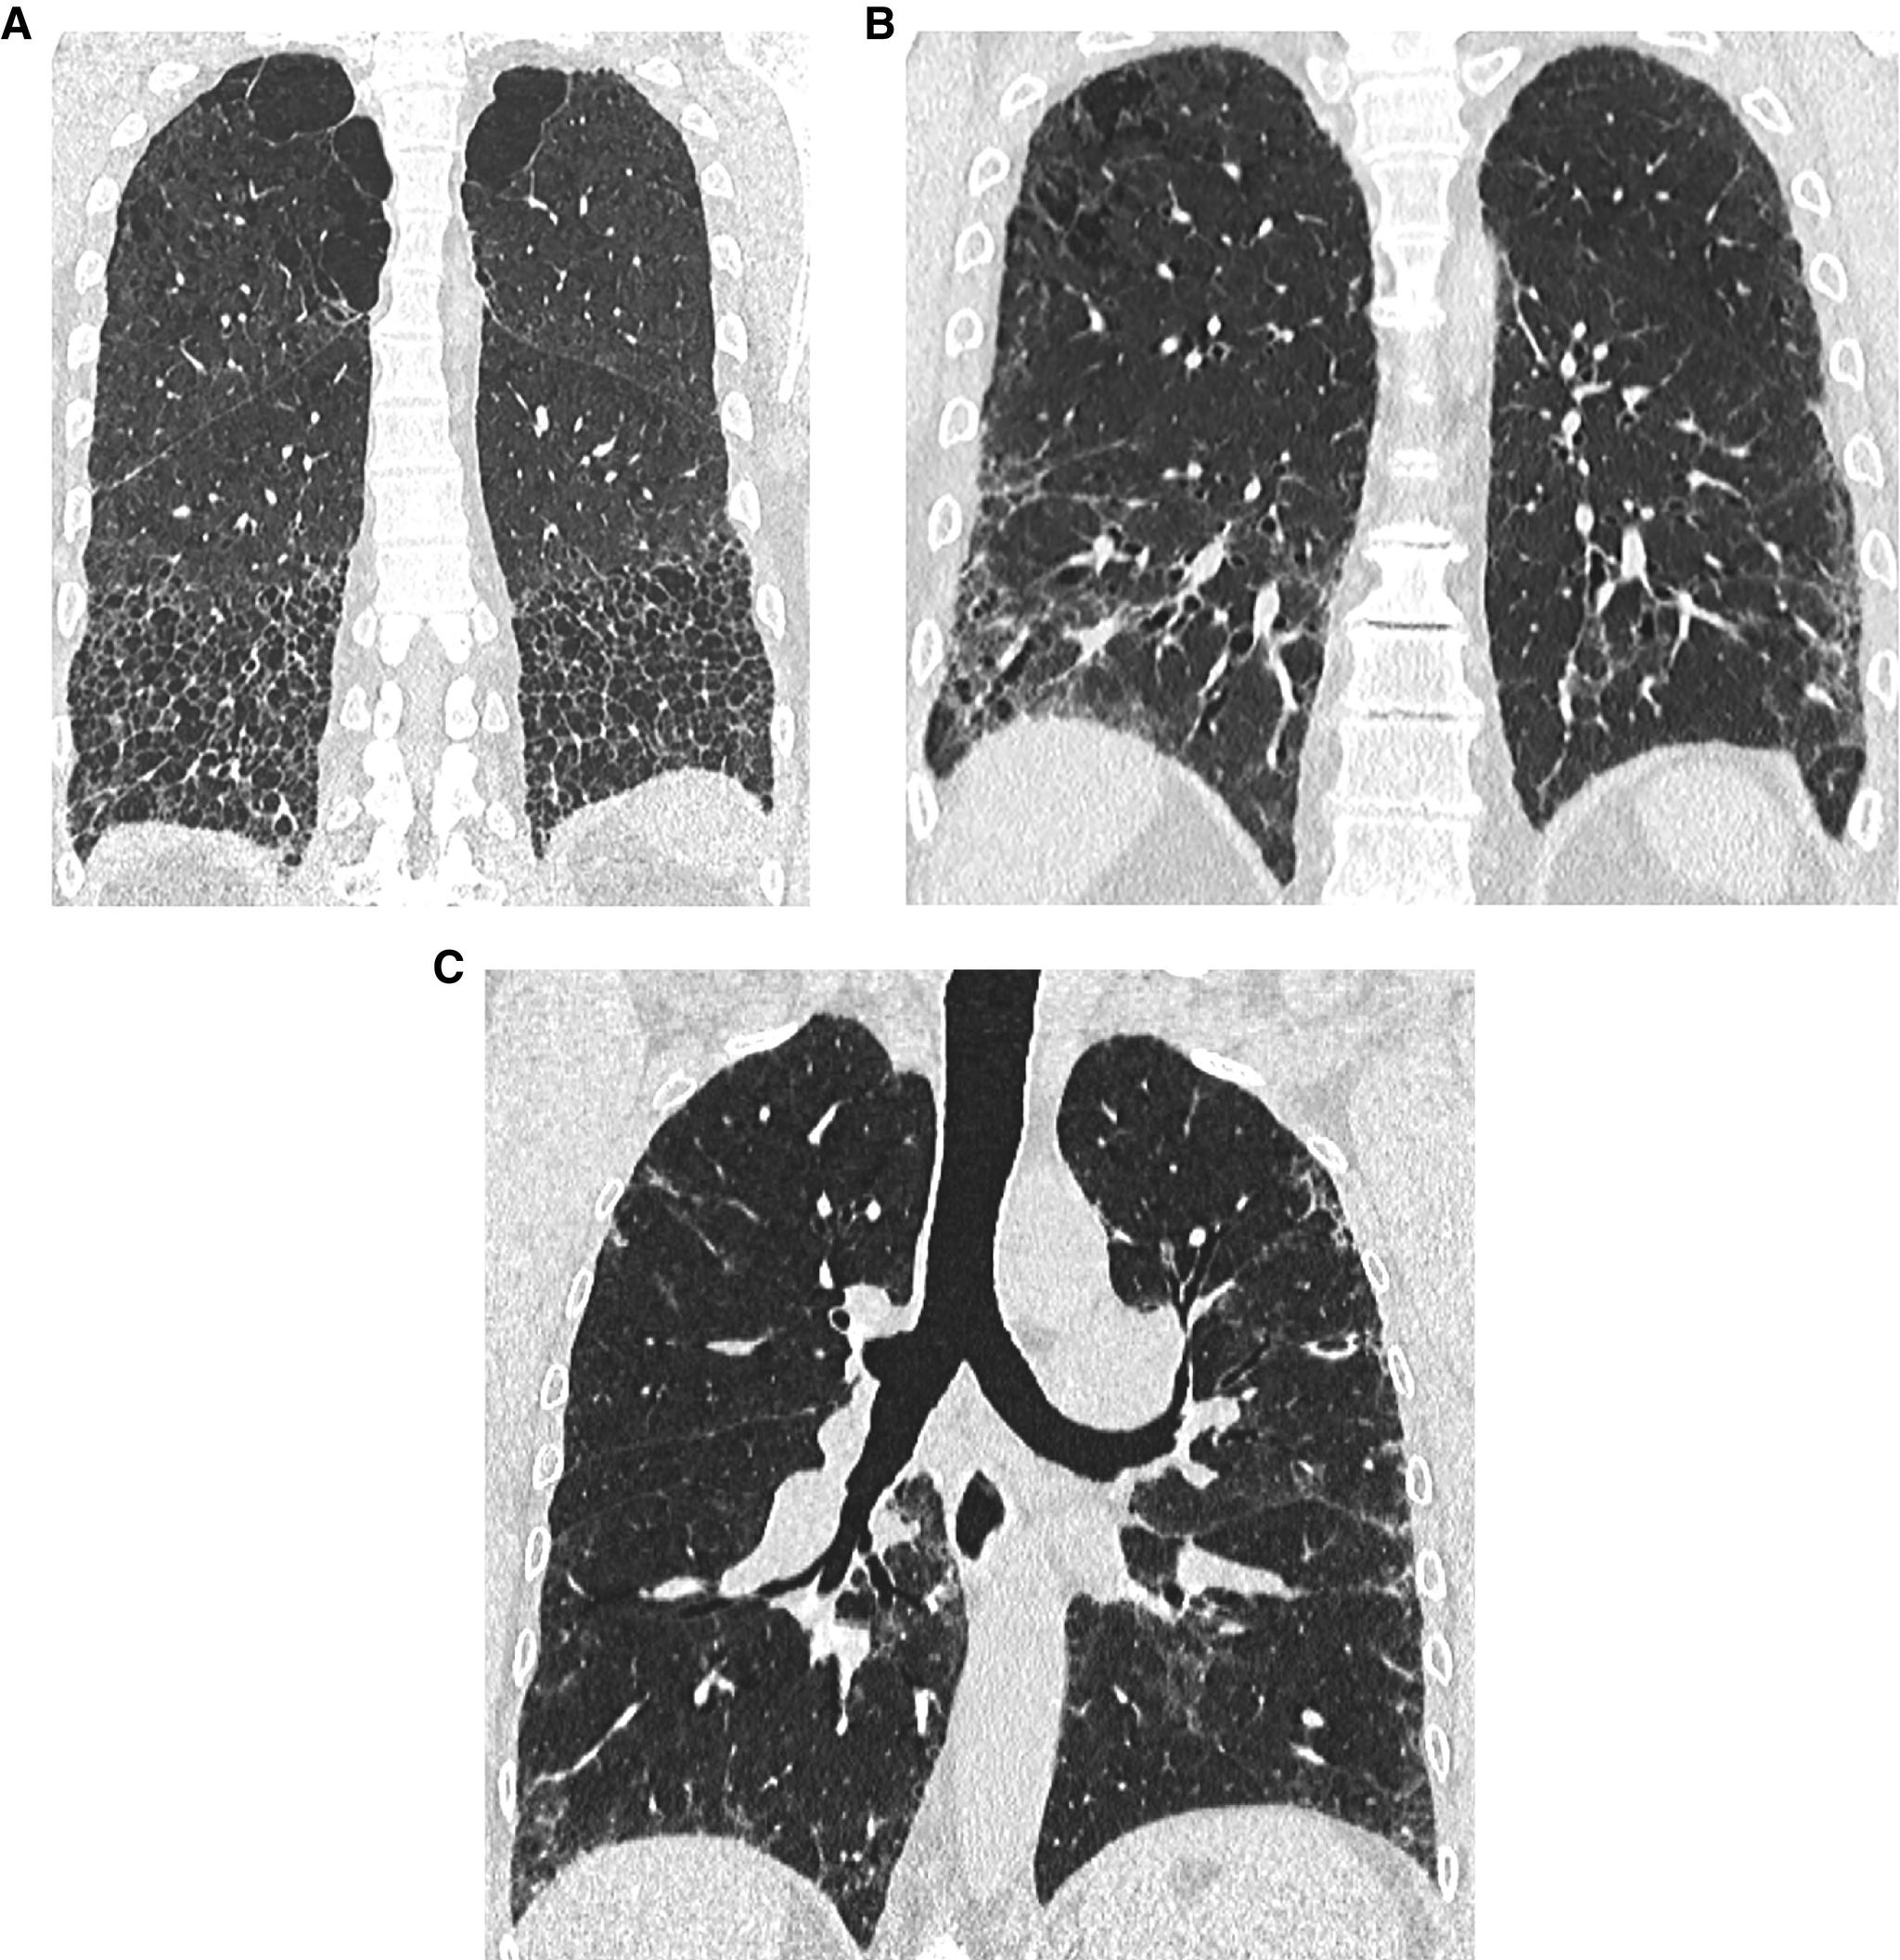

This American Thoracic Society, European Respiratory Society, Japanese Respiratory Society, and Asociación Latinoamericana de Tórax guideline updates prior idiopathic pulmonary fibrosis (IPF) guidelines and addresses the progression of pulmonary fibrosis in patients with interstitial lung diseases (ILDs) other than IPF. A committee was composed of multidisciplinary experts in ILD, methodologists, and patient representatives. ) Update of IPF: Radiological and histopathological criteria for IPF were updated by consensus. Questions about transbronchial lung cryobiopsy, genomic classifier testing, antacid medication, and antireflux surgery were informed by systematic reviews and answered with evidence-based recommendations using the Grading of Recommendations, Assessment, Development and Evaluation (GRADE) approach. ) Progressive pulmonary fibrosis (PPF): PPF was defined, and then radiological and physiological criteria for PPF were determined by consensus. Questions about pirfenidone and nintedanib were informed by systematic reviews and answered with evidence-based recommendations using the GRADE approach. ) Update of IPF: A conditional recommendation was made to regard transbronchial lung cryobiopsy as an acceptable alternative to surgical lung biopsy in centers with appropriate expertise. No recommendation was made for or against genomic classifier testing. Conditional recommendations were made against antacid medication and antireflux surgery for the treatment of IPF. ) PPF: PPF was defined as at least two of three criteria (worsening symptoms, radiological progression, and physiological progression) occurring within the past year with no alternative explanation in a patient with an ILD other than IPF. A conditional recommendation was made for nintedanib, and additional research into pirfenidone was recommended. The conditional recommendations in this guideline are intended to provide the basis for rational, informed decisions by clinicians.

美国胸科学会、欧洲呼吸学会、日本呼吸学会和拉丁美洲胸科学会更新了特发性肺纤维化(IPF)指南,涵盖了除 IPF 以外的间质性肺疾病(ILD)患者肺纤维化的进展。一个委员会由ILD 的多学科专家、方法学家和患者代表组成。

• 更新 IPF:通过共识更新了 IPF 的放射学和组织病理学标准。关于经支气管肺冷冻活检、基因组分类器检测、抗酸药物和抗反流手术的问题,通过系统评价提供信息,并使用基于证据的推荐和 Grading of Recommendations, Assessment, Development and Evaluation (GRADE) 方法回答。

• 进行性肺纤维化(PPF):定义了 PPF,然后通过共识确定了 PPF 的放射学和生理学标准。关于吡非尼酮和尼达尼布的问题,通过系统评价提供信息,并使用基于证据的推荐和 GRADE 方法回答。

• 更新 IPF:有条件建议将经支气管肺冷冻活检视为具有适当专业知识的中心替代外科肺活检的可接受方法。未对基因组分类器检测提出建议或反对。有条件反对使用抗酸药物和抗反流手术治疗 IPF。

• PPF:PPF 定义为在过去一年中,在非 IPF 的ILD 患者中,出现至少三个标准中的两个(症状恶化、放射学进展和生理学进展),且无其他解释。建议使用尼达尼布,并建议对吡非尼酮进行进一步研究。